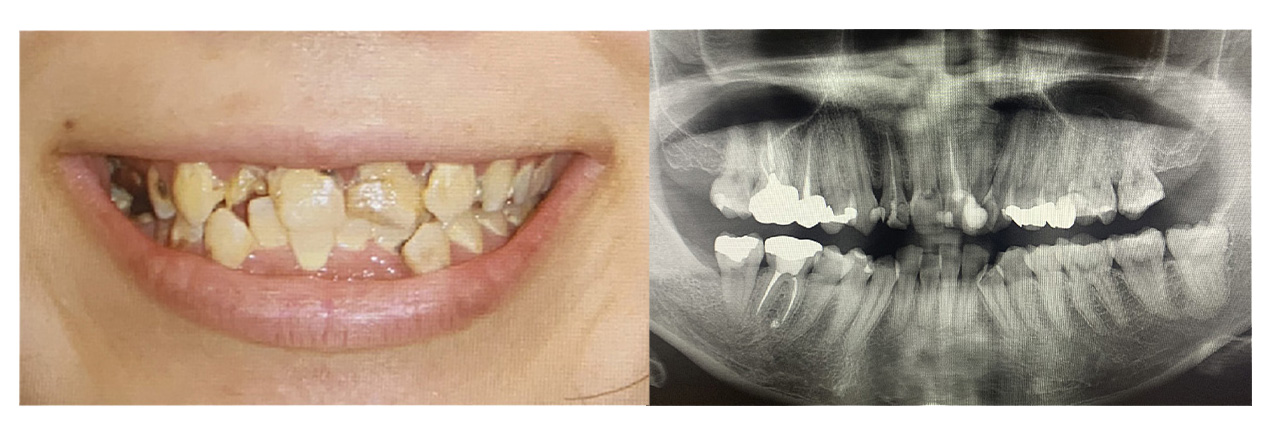

症例写真の紹介

ここで、当院がこれまでに治療してきたオールオン4やザイゴマの症例写真をご覧ください。お口の状況がどれほど改善されるかがイメージしやすくなるかと思います。

症例⑥オールオン4

• Before

• After

疼痛、審美障害。全体的に虫歯でボロボロな歯を全部抜歯してオールオン4で治療した症例。